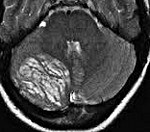

Диагностика болезни Лермитт-Дуклос производится посредством выявления характерных образований в мозжечке при помощи компьютерной и магнито-резонансной томографии. На КТ головного мозга при этом выявляется объемное гиперденсивное образование с размытыми и нечеткими краями, которое может быть расположено как на поверхности, так и в глубине мозжечка. МРТ головного мозга лучше всего производить с внутривенным контрастированием, поскольку именно такой метод позволит наилучшим образом изучить структуру и сосудистую сеть новообразования. При отсутствии технической возможности проведения данных исследований можно сделать рентгеновскую вентрикулографию - как правило, она показывает уменьшение или смещение четвертого желудочка и водопровода. Однако при незначительном размере ганглиоцитомы таких изменений может и не быть, поэтому вентрикулография не считается основным методом диагностики болезни Лермитт-Дуклос.

Кроме того, по возможности (например, при поверхностном относительно мозжечка расположении опухоли) выполняют биопсию образования с последующим гистологическим изучением. Подобные исследования последних лет выявили, что ганглиоцитома мозжечка при болезни Лермитт-Дуклос представляет собой гамартому. В ее структуре наблюдается расширение молекулярного слоя и заполнение его ганглиозными клетками. Врачи-генетики также производят секвенирование последовательности гена PTEN, которое выявляет наличие или отсутствие в нем мутаций. Исследование наследственного анамнеза тоже может помочь в диагностике болезни Лермитт-Дуклос - при этом стоит обращать внимание на косвенные признаки заболевания, учитывая возможность бессимптомного течения. К ним относятся наличие у ближайших родственников поли- и синдактилии, мегалоцефалии, гиперплазии десен.